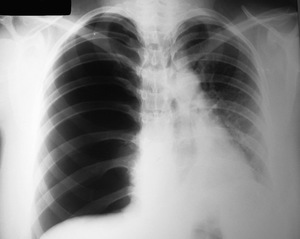

Pneumotórax Hipertensivo

Sinais? (6)

Qual a conduta IMEDIATA para o Pneumotórax Hipertensivo?

Atualização ATLS 2018

Toracocentese de Alívio no 5º EIC na

Linha Axilar Média.

Conduta definitiva?

Toracostomia + Drenagem em selo d’água

(5º EIC na Linha Axilar Anterior Média)

Qual a condição para formação de um Pneumotórax Aberto?

Pneumotórax Aberto

Conduta imediata?

Curativo de 03 pontas

imediatamente

Toracostomia.

(Drenagem torácica).